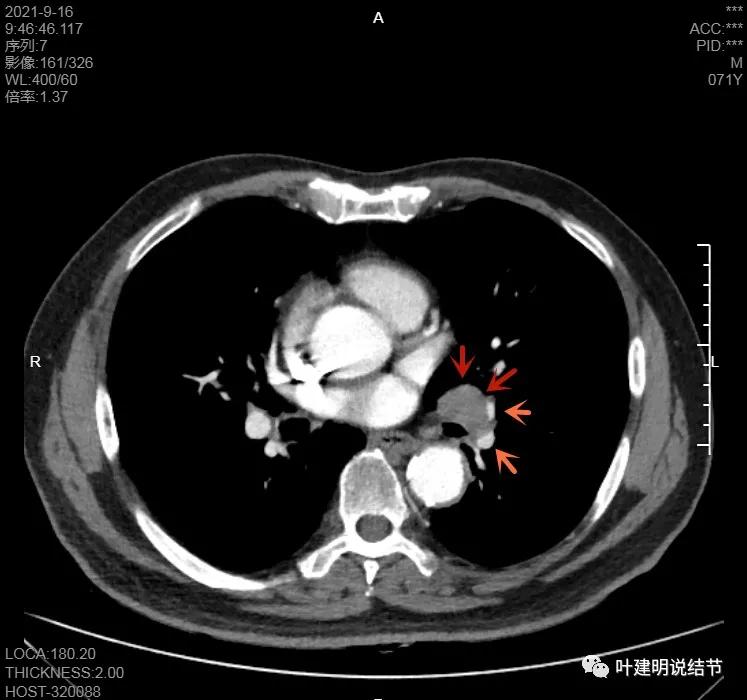

左下病灶在增强CT中强化不明显,但有肺门区肿大淋巴结,而且近3厘米大。同事叫我看片子的时候,本来只先看左下病灶处,以为是良性结节。但翻到肺门区,发现有如此大的肿大淋巴结,那这个原发灶则肯定是恶性的了!我们先来看纵隔窗的淋巴结情况:

左肺门区淋巴结肿大

肺门区淋巴结挤压附近肺血管,但似乎示见肿瘤侵犯破坏血管壁

淋巴结巨大,部分包绕肺血管,但仍未见明显侵犯血管壁

肺血管受压明显,气管内壁感觉也是光滑的

以上诸图均示肿大淋巴结挤压肺血管,但未见确切侵犯破坏,支气管内壁也感觉是光滑的,没有肿瘤突向管腔